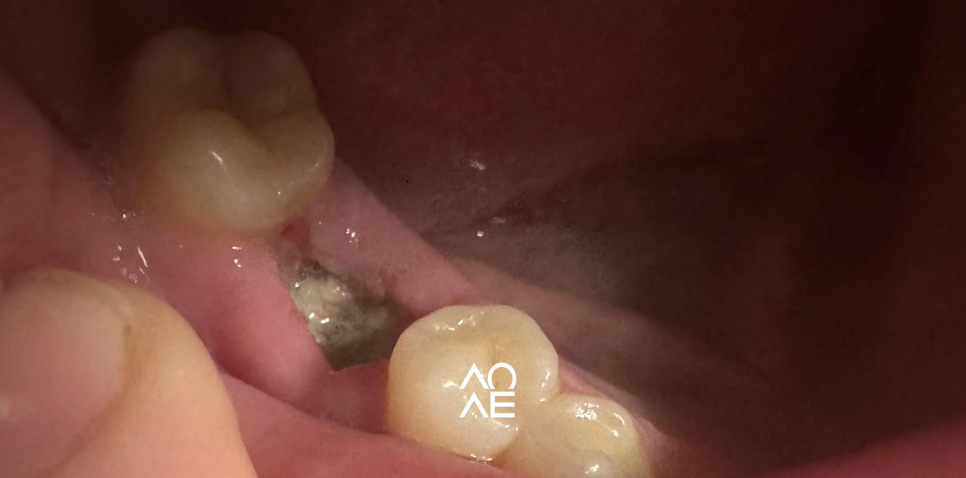

혈병이 한 번 빠진 자리는

다시 혈병이 생성되지 않아요

봉합사를 제거하고,

식염수로 발치 부위를 세척하고

3~4주 정도 클로르헥시딘으로

깨끗하게 유지시켜야 하는데

이 걸 집에서 하실 수 없죠?